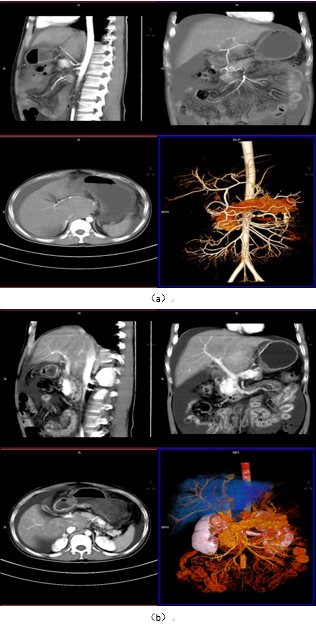

图1成像方式是目前大多数医院常规采取的扫描方式,满足对疾病的诊断,我中心当前采用的也是此类扫描方式,主要适用于常规检查、诊断,临床需求不单纯是提供诊断、还需要了解病灶与比邻组织器官关系,尤其是与大血管间的关系,制定最优化的手术方案,更快捷、安全、有效的进行手术治疗,但普通扫描在血管区分上欠佳。图2-9为肝脏CT一体化成像图,能更好的区分肝动脉、门脉、胆总管等结构,加上延迟扫描对正常组织器官及病变的显示影响有限,结合3D可视化图像,为临床医师手术提供精准化的参考、制定精准化的手术路径,为患者减少术后并发症。

图2:一体化成像扫描肝动脉、门脉显像(VRT/MPR)

7:肝脏3D可视化

8:肝脏3D可视化